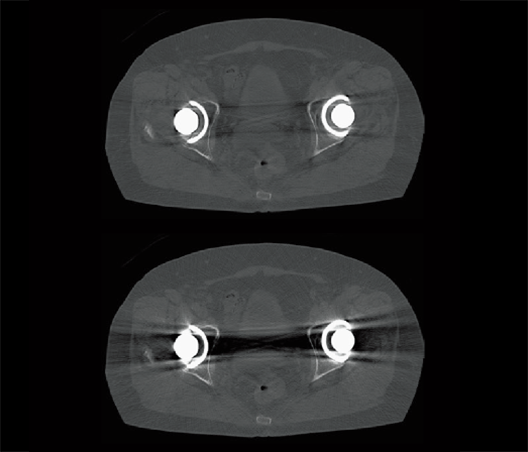

Articulación de la cadera (HiMAR Plus)